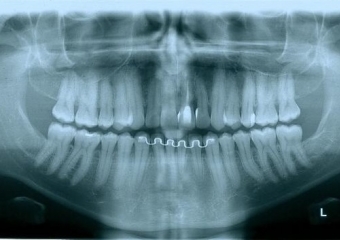

Rx Panoramico Inicial 15-06-15